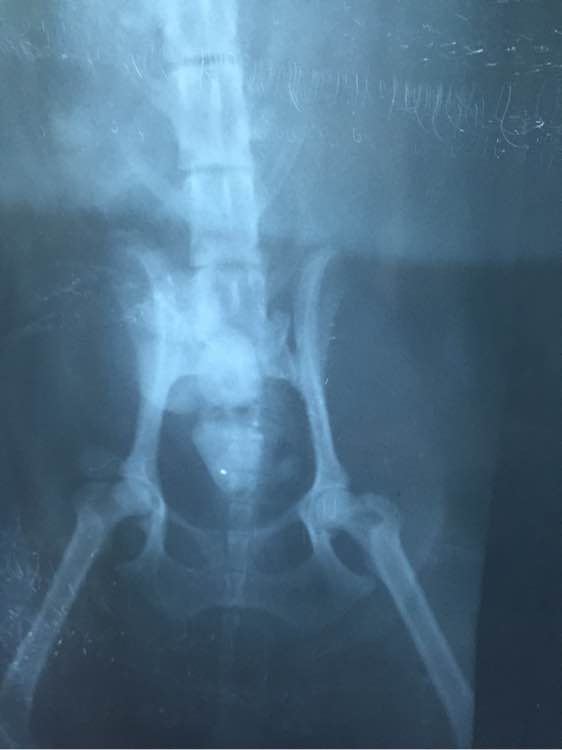

这只捡到的泰迪,今天做了B超和X光尿道,医生说可能是膀胱结石,明天就要开刀动手术了,可能以后都不会再捡狗狗了,一月工资半月花狗狗身上,希望以后不会看到狗狗流浪,即使狗狗生病了也不会被遗弃~

手术做的很成功,但是取出来的东西真的很恐怖,都是结石~